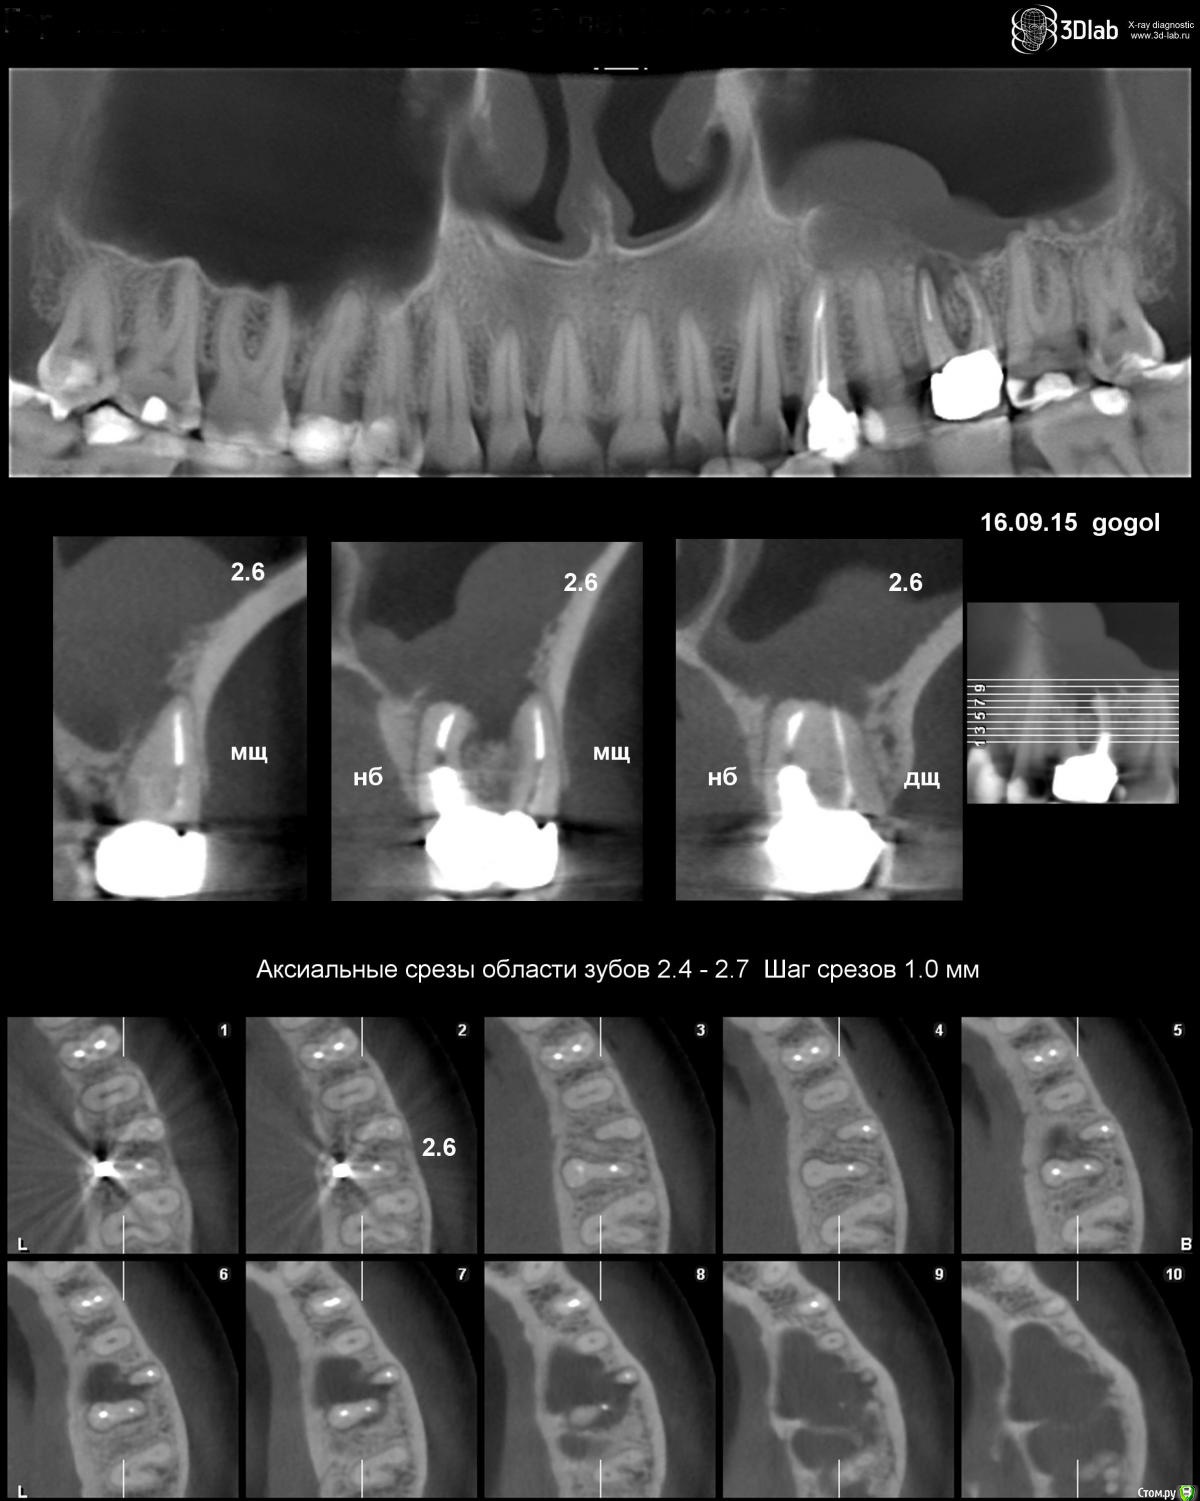

Olga_bou Опубликовано 22 сентября, 2015 Поделиться Опубликовано 22 сентября, 2015 Здравствуйте, уважаемые стоматологи, Пожалуйста, посоветуйте, как быть в моей ситуации. Дано: верхний 6 зуб слева, строго говоря, не зуб, а корни, над десной уже нет ничего, на золотой культевой вкладке стоит коронка. Поставили полтора года назад. Пару недель назад зуб стал чувствителен, боль при надавливании, чувство подросшего зуба, боль терпимая, но непроходящая. Пропила антибиотики, боль прошла. Но всегда было понятно, что если что-то с этим зубом случится, то удалять его. Вот, похоже, момент настал. Врач отправил на КТ. Т.к. планировалось удаление, потом заживление, потом имплантация. Причем сказал, что посмотрит КТ и решит, сможет ли он в условиях клиники удалить или направит в стационар, т.к. корни в пазухе могут быть, и не исключена перфорация пазухи. Сделала КТ, которое показывает кисту в пазухе. Т.е. при удалении зуба и чтоб до кисты добраться перфорация пазухи все равно будет?До врача смогу добраться только через неделю. Поэтому вопрос, действительно ли лучше в стационар? Какая вообще техника удаления в моем случае будет с учетом того, что в будущем я бы хотела имплант поставить? Чего ожидать и к чему готовиться? Через дырку от удаленного зуба до кисты смогут добраться? И еще, можно ли по этому снимку (КТ) определить, что киста именно одонтогенная или что с такими кистами только к ЛОРу? Снимок прилагаю. Ссылка на комментарий

IvanK Опубликовано 23 сентября, 2015 Поделиться Опубликовано 23 сентября, 2015 Здраствуйте перфорация пазухи все равно будет? не обязательно действительно ли лучше в стационар? удаление не требует стационара Какая вообще техника удаления в моем случае будет с учетом того, что в будущем я бы хотела имплант поставить? аккуратное удаление что киста именно одонтогенная одонтогенная 1 Ссылка на комментарий